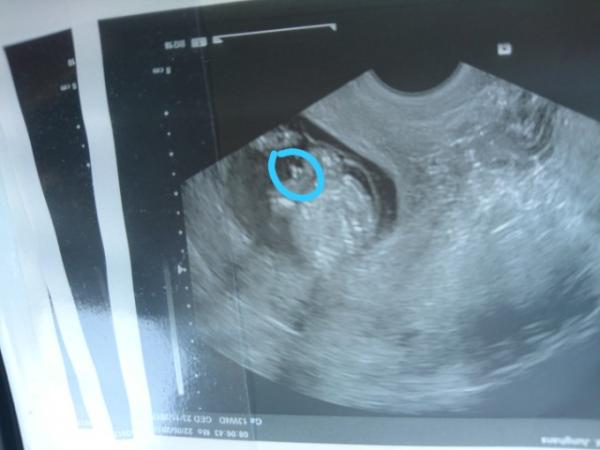

Hallo ihr lieben, ich war am Montag bei meinem FA zum ganz normalen Ultraschall. Der kleine war ziemlich aktiv und sie meinte mal schauen ob wir zwischen die Beine gucken können. Dazu muss ich sagen da war ich 13+4. Sie meinte es sieht wohl sehr danach aus das es ein Junge wird. Hatte das jemand von euch vielleicht auch und kann man sich darauf so gut es geht verlassen? Ich finde es nämlich schon ziemlich früh das jetzt schon festzustellen. Hab hier noch mal das Ultraschall Bild dran gehangen.

Bild zu Geschlecht erkennen! - Schwanger - wer noch? Rund um die Schwangerschaft